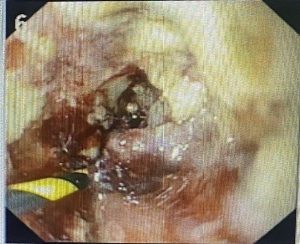

MỘT SỐ HÌNH ẢNH TRONG QUÁ TRÌNH ĐIỀU TRỊ BỆNH NHÂN

Hình 2. Nong bóng qua nội soi vị trí hẹp thực quản do ung thư xâm lấn. Sau khi nong, ống soi đưa được qua chỗ hẹp xuống dạ dày, bệnh nhân ăn uống tốt hơn sau can thiệp